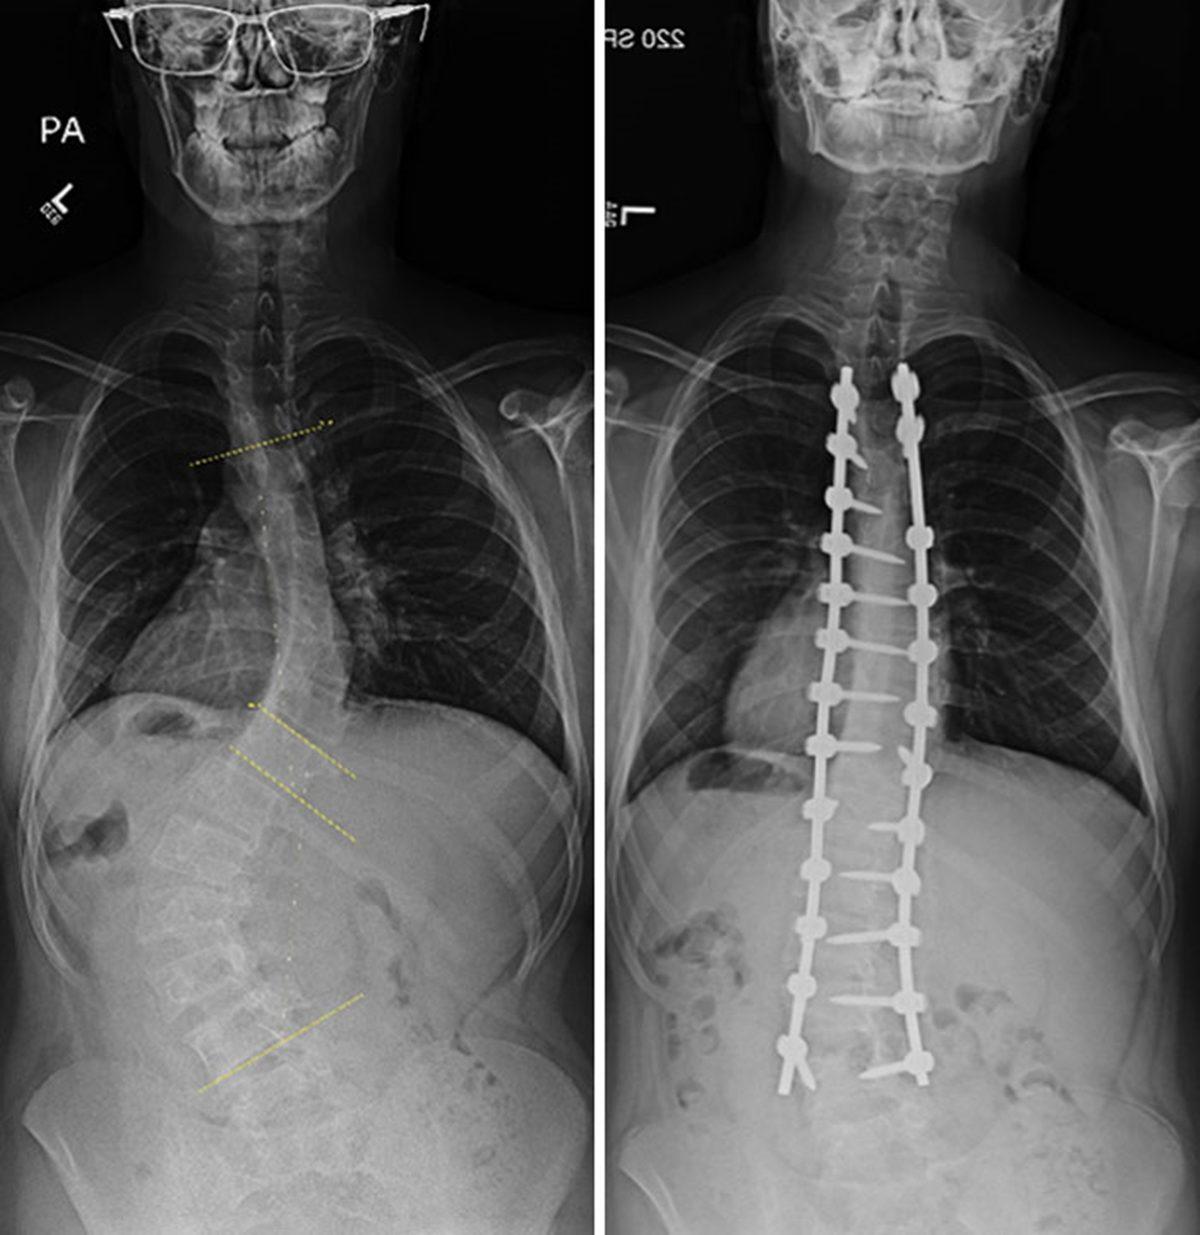

- Skolyoz rahatsızlığı olan biri.

Normalde böyle görünüyor: